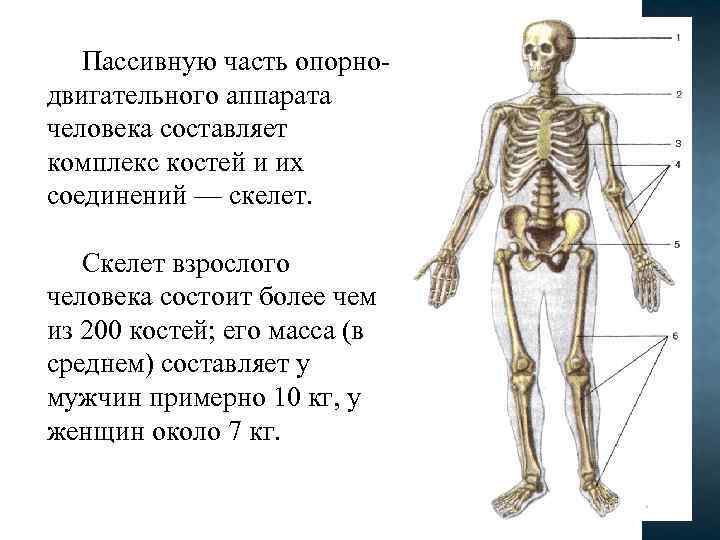

Пассивную часть опорнодвигательного аппарата человека составляет комплекс костей и их соединений — скелет. Скелет взрослого человека состоит более чем из 200 костей; его масса (в среднем) составляет у мужчин примерно 10 кг, у женщин около 7 кг.